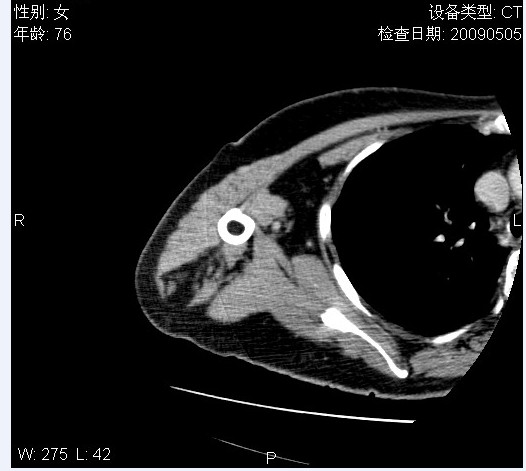

标题: CT19811:女,76岁,右上臂肿物1个月 [打印本页]

标题: CT19811:女,76岁,右上臂肿物1个月

使用了造影剂,可惜效果不太好

右肱骨上段软组织内见梭形低密度影,边界清楚,最长径约54mm.

病理结果:脂肪瘤。术中见肱骨骨膜受侵,有出血,量不详。

当时诊断意见:右肩三角肌内蔓状血管瘤(先天性动静脉瘘)。

本人对病理结果有个疑问:单纯的脂肪瘤内为什么有条状软组织影,那应该脂肪肉瘤才对啊?

该病例增强效果欠佳,由于经验欠缺,我们注射对比剂是由下肢足背静脉给药。注速2.0。虽然如此,但我们可以看到肿块内部条状软组织影是强化的,而且是连续的,并可见供血动脉是由腋动脉的其中一支即肩胛下动脉分出。从这些征象我们可以得出诊断:蔓状务血管瘤。

可病理偏偏为脂肪瘤,我怀疑取材有问题。因为蔓状血管瘤异常扩张的静脉外周是脂肪成分,它可以侵犯肌组织及骨骼。当取材于外周,那当然是脂肪瘤。此时我认为临床的最终诊断不应单从病理出发,应该综合考虑。